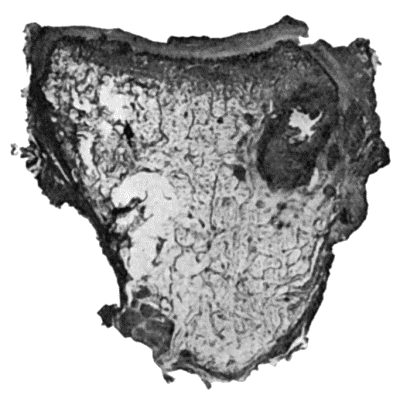

114.Section through Gouty Bursa 428

115.Tuberculous Disease of Sub-Deltoid Bursa 429